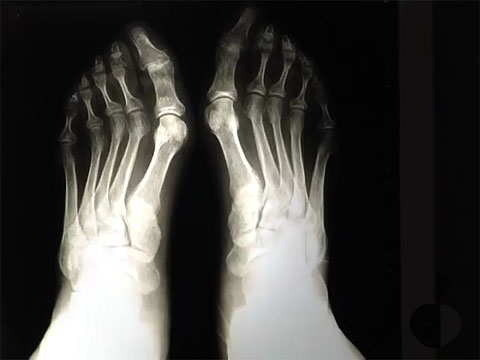

La Salud empieza por los pies - 24/11/10

El doctor Juan Pablo Giménez resuelve todas sus dudas y le da los mejores consejos para que cuide sus pies, un elemento fundamental de su salud. Un espacio presentado por Belén Morales en el que puede participar en directo.